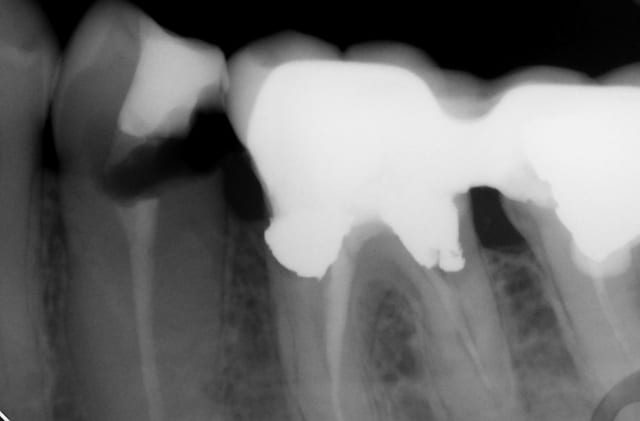

Bref je fais l'endo, et lisant de plus en plus de choses sur le sans-tenon (surtout le risque de fracture supérieur qu'il engendrait par perte de substance dentinaire) je me suis lancé dans un "Nayyar" core, compo descendant dans les entrées canalaires et par dessus une CCC.

Ci-joint les radios.

PS: Légère extrusion de pâte en distal, j'ai un peu forcé sur le Mac Spadden, faut que je m'équipe du système B...